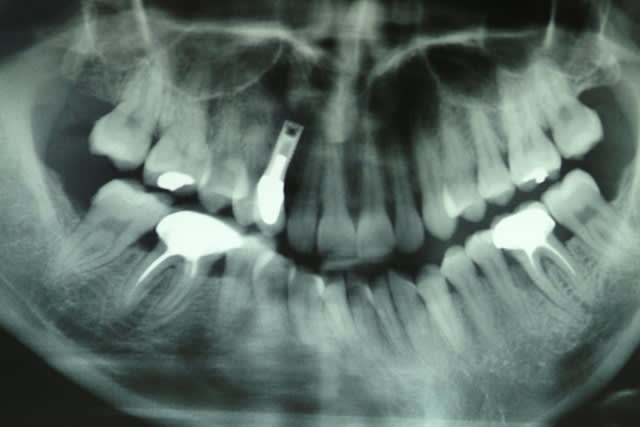

Implant sur la 13 posé il y'à 15 ans.

La 13 était dans le palais, extraite qqs mois avant l'implantation.

j'ai juste une pano, mais rien de spécial dessus, implant cylindrique, à vue d'oeil, diam 4, long 10 à 12 mm.

Il me semble que c’est le liserai du pilier qui est visible, que l’ajustage la couronne soit perfectible et que l’on aperçoive légèrement l’implant.

L’espace entre 12 et 14 est trop faible pour aligner la 13 qui est trop courte sur bord incisif.

Voici les clichés de l'implant sur 13

marcB6

çà ressemble à un des premiers screwvent (paragon...zimmer )